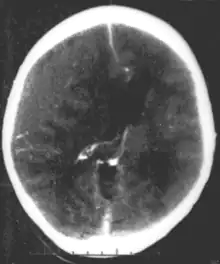

Brain trauma in the developing human is a common cause (over 400,000 injuries per year in the US alone, without clear information as to how many produce developmental sequellae)[64] of neurodevelopmental syndromes. It may be subdivided into two major categories, congenital injury (including injury resulting from otherwise uncomplicated premature birth)[65] and injury occurring in infancy or childhood. Common causes of congenital injury are asphyxia (obstruction of the trachea), hypoxia (lack of oxygen to the brain), and the mechanical trauma of the birth process itself.[66]